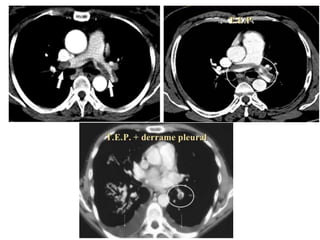

TAC Helicoidal Es latécnica de elección. Permite la visualización directa del trombo dentro de la arteria pulmonar y sus ramas.

Angio TAC querevela un trombo oclusivo en el tronco de la arteria pulmonar derecha y trombos menores en la arteria pulmonar izquierda (flechas).